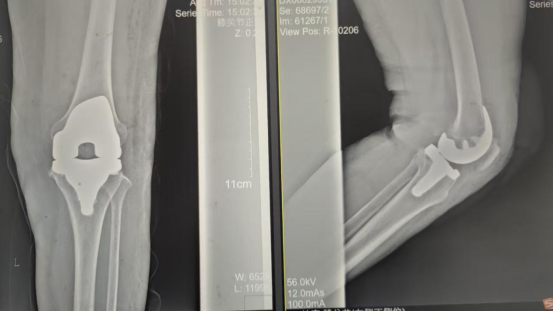

術(shù)后影像資料

因張女士患有高血壓病2級(高危)、心律失常(竇緩)且伴有肺部感染等并發(fā)癥。穆志亮主任和葉龍安主治醫師根據張女士的病情制定詳細手術(shù)方案,建議在全麻下行“左人工全膝關(guān)節置換術(shù)”。

手術(shù)當天張女士懷著(zhù)忐忑的心情進(jìn)入手術(shù)室,然而伴隨著(zhù)麻醉醫師的和藹交談和手術(shù)護士的溫馨叮嚀,在不知不覺(jué)中慢慢睡著(zhù),手術(shù)非常順利。術(shù)后經(jīng)醫護人員的精心治療與護理,張女士康復出院,最終解決了10余年的病痛。